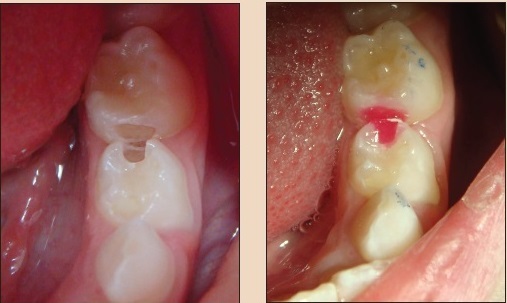

Пломбирование молочных зубов: фото до и после

Невычищенные зубы, неудаленный вовремя налет – это причина множества заболевания и осложнений. Бактерии быстро разъедают эмаль, проникая в глубокие слови дентина, разрушая зуб и поражая его нерв. Лечение и пломбирование молочных зубов у детей – такая же необходимость, как и коренных у взрослых. У нас есть весь арсенал средств, которые помогут сделать лечение приятным и веселым – например, цветные детские пломбы. Помните, что зубы малышей гораздо более подвержены агрессивному воздействию внешних факторов.

Словом, и профилактика, и лечение, в том числе пломбирование молочных зубов – это обязательная процедура в детском графике врачебных посещений. Остается ответить на один вопрос – где это можно сделать? Малышам и ребятам постарше нужен свой врач. Поэтому мы приглашаем вас к нам, в клинику Дока-Дент, где есть специальные детские врачи, которые не только профессионально более подкованы в работе с детьми, но и всегда найдут подходу даже к самому большому капризуле. Не секрет, что визит к стоматологу – не самая приятная процедура. Поэтому мы постарались в буквальном смысле делать ее ярче. У нас уникальная подборка цветных детских пломб, и малыш сам сможет выбрать понравившуюся.